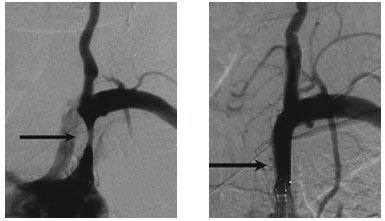

发现锁骨下动脉狭窄或闭塞后又该如何治疗?首选需要找到血管外科医生进行专科查体及相关检查,如血管彩超,CTA或者DSA检查,最终判断是否存在锁骨下动脉窃血。一旦诊断明确,需要及时手术治疗,预防缺血性脑卒中的发生。目前手术首选腔内支架植入,创伤小,恢复快,局麻下即可解除您的病患。

严重的锁骨下动脉狭窄或闭塞,不仅仅出现上肢血压下降,最重要的是导致锁骨下动脉窃血综合征,即指在锁骨下动脉或头臂干的椎动脉起始处的近心段有部分的或完全的闭塞性损害,由于虹吸作用,引起患侧椎动脉中的血流逆行,进入患侧锁骨下动脉的远心端,导致椎-基动脉缺血性发作和患侧上肢缺血性的症候。可以有脑缺血或上肢缺血症状,甚至缺血性脑卒中(示意图如下)。